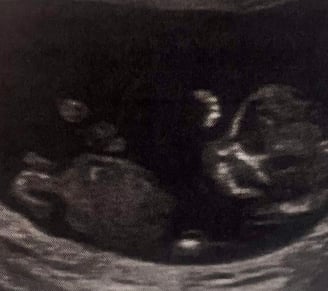

IGNOTO 3 (COOMING SOON)